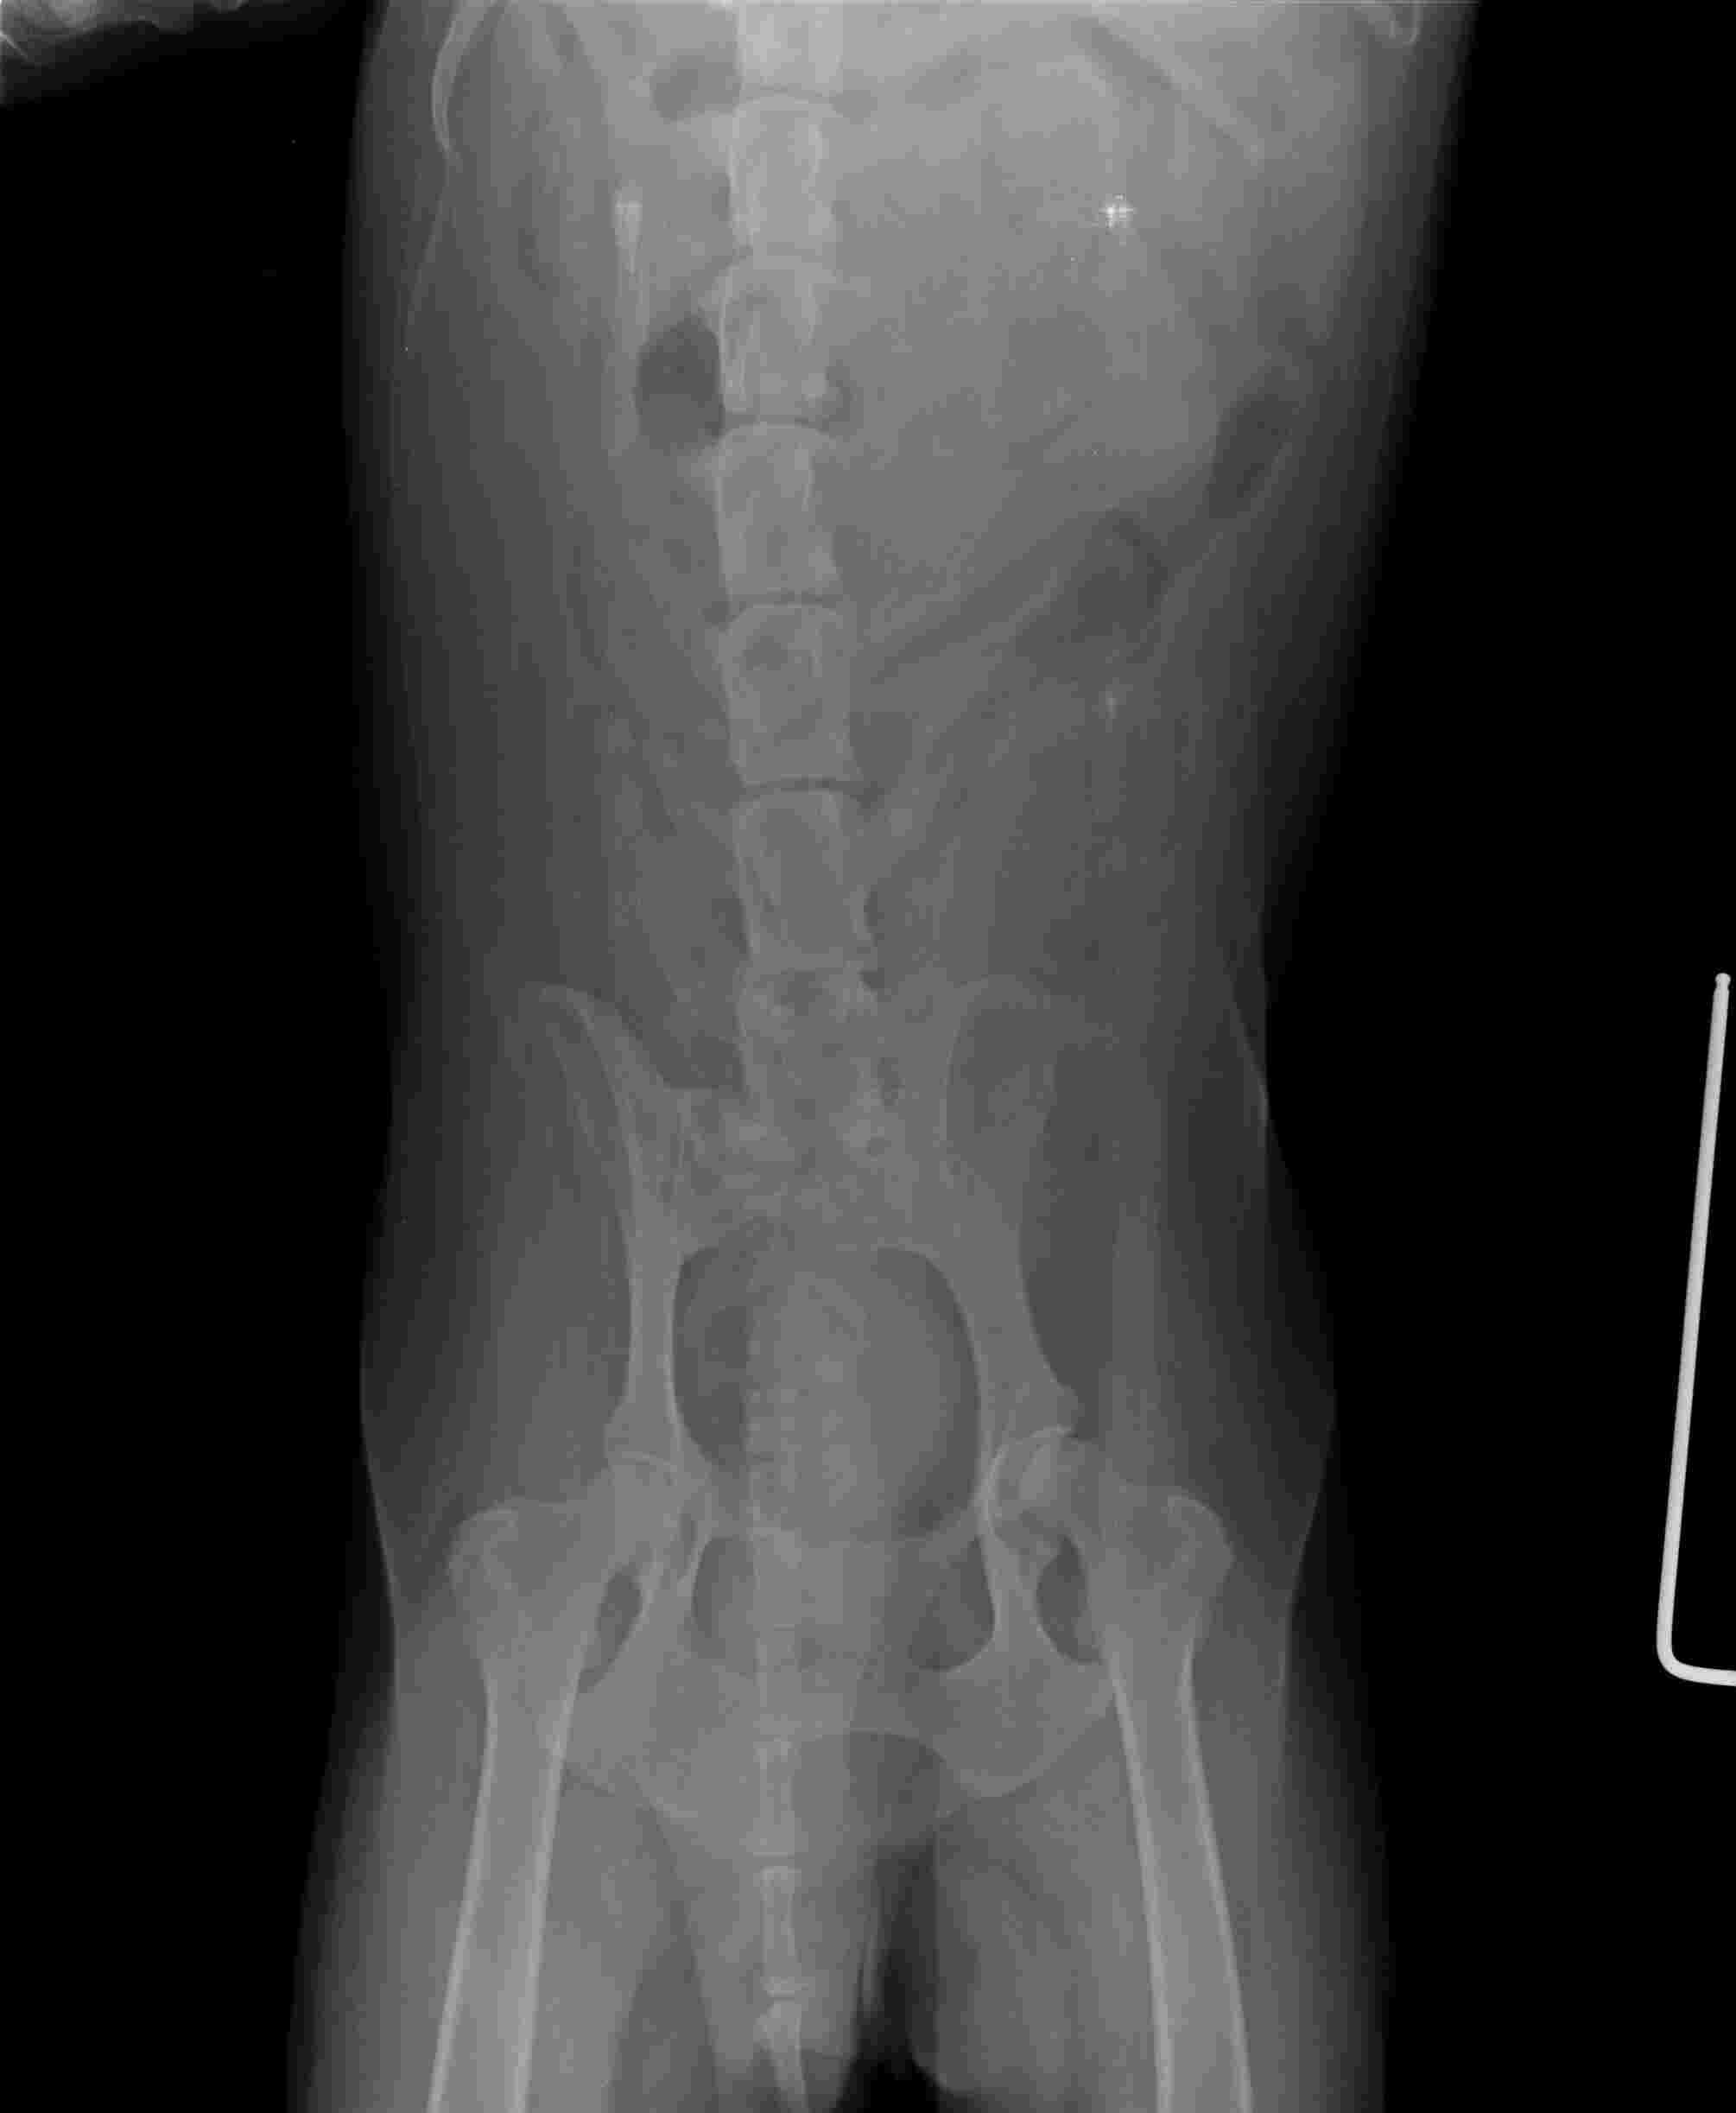

Hello, i have a husky female, she is 9 years old, in december she had the operation spayed and removal of a tumour in her breast in the same time both of them, since then the walking was not that good anhmore she barely could of and in the same time we went visitong her and she has arthrithis, now she barely can stay she can not walk anymore plase tell.me what can i do beside painkillers and supplements, i need some natural organic treatments a quick one please help

This question includes photos that may contain sensitive content. Click to view.